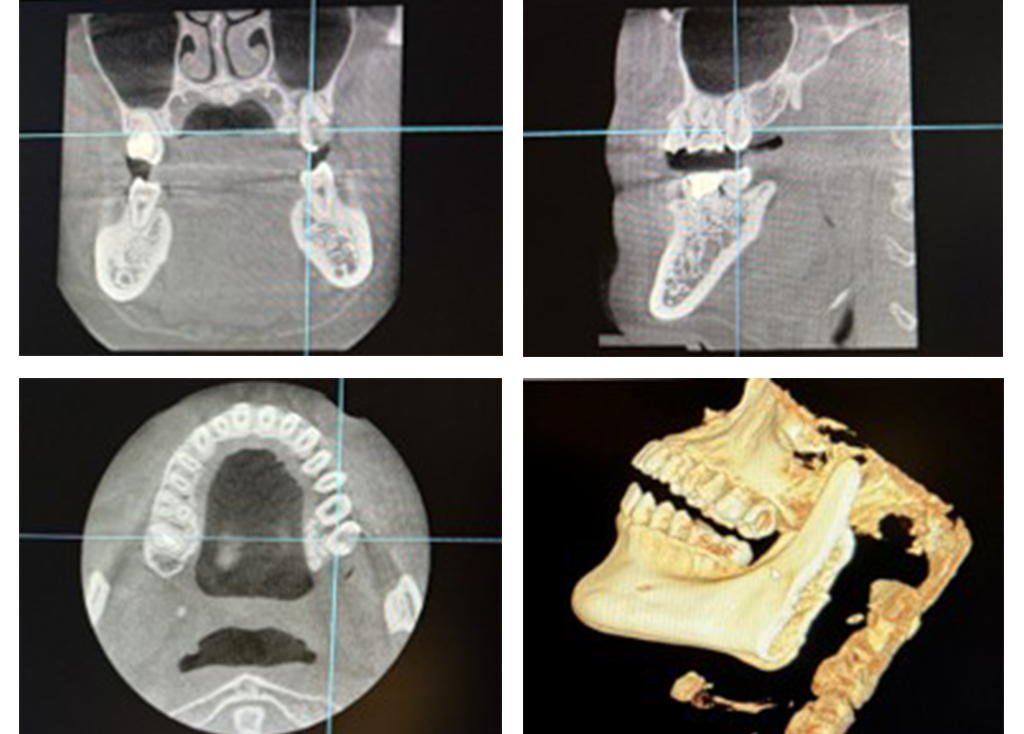

精密な根管治療

それに対応すべく、当院では米国で主流となっているNiTiファイルを用いた根管治療を取り入れております。

CTとマイクロスコープを使用